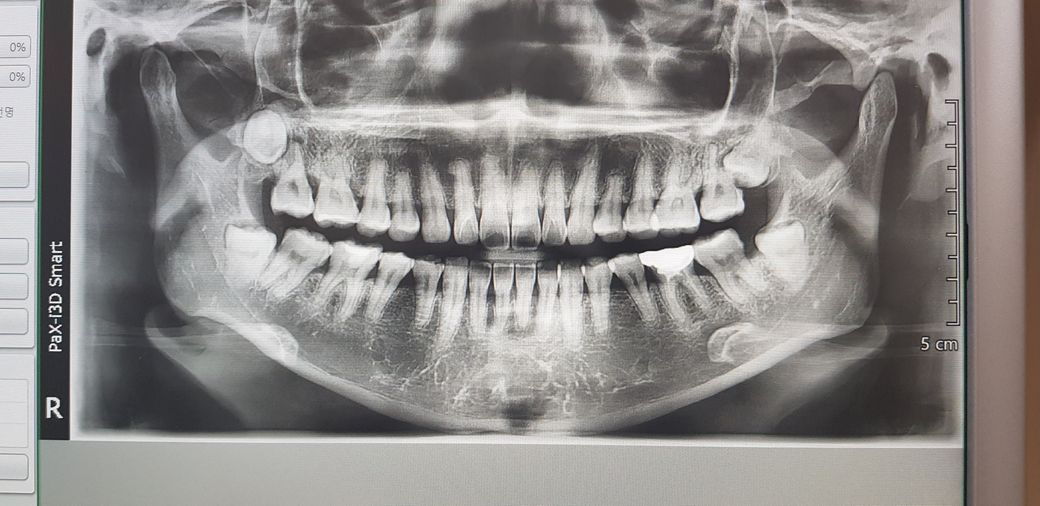

제 치아 사진입니다.

사랑니가 어금니의 신경을 누르고 있는거처럼 보이는데..

전문가님들이 모시기엔 어떠세요???

왼쪽 위의 어금니가 아프신것인지 아래가 아프신것인지 모르겠으나, 사랑니가 앞치아의 신경을 누르는것같다는 말씀을 보아 위쪽이 아프신것으로 보입니다.

왼쪽위의 사랑니는, 씨티를 찍어봐야 정확히 알 수 있겠으나, 앞의 치아와 닿아있는 듯이 보입니다.

또한, 사랑니가 매복이 되어있다보니까, 그 앞치아를 감싸고 있는 잇몸뼈가 부족해보입니다.

오른쪽 위의 사랑니 앞치아도 상태가 좋아보이진 않습니다.

오래전부터 사랑니가 매복된 상태에서 앞의 치아를 누르고 있는상태로 지내셨고 그동안 통증이 없으셨으나, 만약 통증이 생겼다면 통증의 원인을 찾아서 적절한 치료가 필요할 것으로 보입니다.